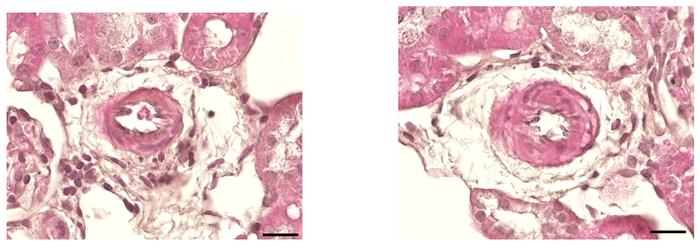

The kidney tissue in the HTNB rats also showed no signs of inflammation or fibrosis (an increased production of connective tissue that causes organs to harden). The transcriptome, which shows what genes are currently active, was also unchanged in the rats’ kidneys. “What we did find is reduced expression of the protein amphiregulin in certain regions of the organ,” says Sholokh. “Since high levels of amphiregulin are likely to damage the kidneys, the suppressed production probably helps to protect them.”